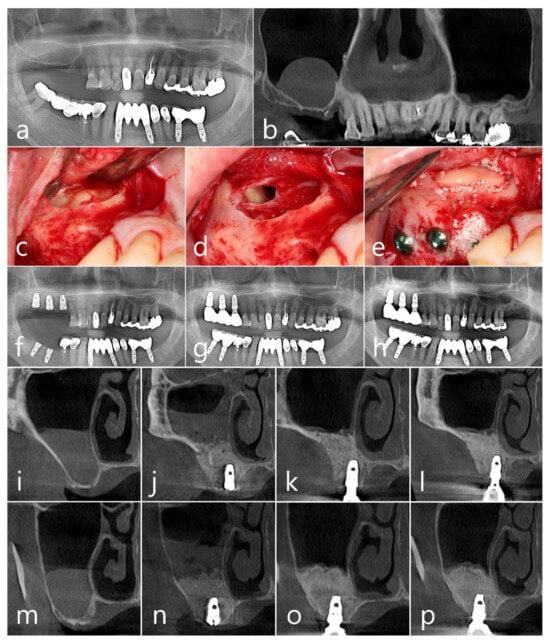

2.1. Case 1